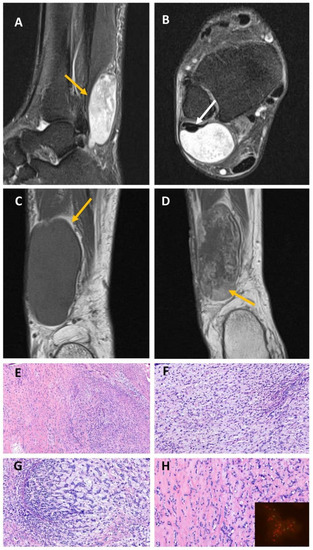

2.3. EWSR1::NFATC2-Rearranged Soft Tissue Sarcoma (Case #4)